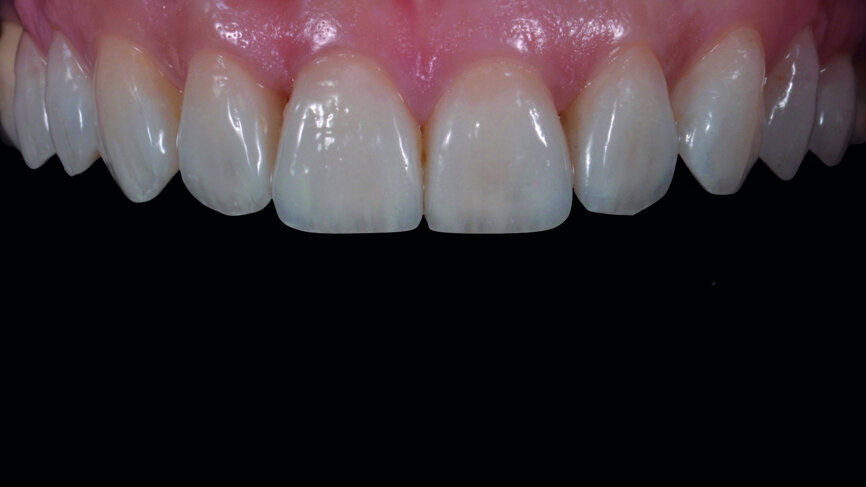

Fig. 1: Initial photograph of the anterior teeth prior to orthodontic treatment.

A 35-year-old patient presented at the office with the chief desire that the aesthetics in the anterior region be changed (Fig. 1). A diagnostic wax-up was performed, followed by mock-up fabrication, in order to obtain a preliminary visualisation of the final outcome. Orthodontic treatment was proposed in order to align the teeth in a more favourable position for veneers requiring minimal preparation and to reduce the overbite. One year after treatment, the patient returned for the final prosthetic rehabilitation (Figs. 2a & b).